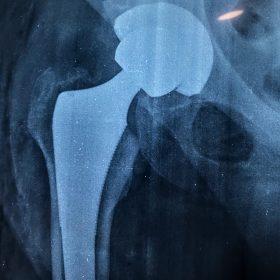

Παραδοσιακά οι αρθροπλαστικές ισχίου αποτελούνται από μια μεταλλική μπάλα – σφαίρα τοποθετημένη σε μια πλαστική κοιλότητα (κοτυλιαία πρόθεση).

Η πλαστική επιφάνεια στήριξης φθείρεται με την πάροδο του χρόνο, με ρυθμό μάλλον σχετιζόμενο με το επίπεδο δραστηριότητας του ατόμου. Αυτό έχει σαν επακόλουθο νεότεροι ασθενείς με μεγαλύτερο προσδόκιμο ζωής να έχουν αυξημένο ρίσκο αναγκαιότητας δεύτερης αρθροπλαστικής ισχίου (αναθεώρησης – Revision) επέμβαση που είναι πολυπλοκότερη και υπόκεινται σε υψηλότερο κίνδυνο επιπλοκών. Βάση των ανωτέρω, ιστορικά, η αρθροπλαστική ισχίου σπανίως εφαρμοζόταν σε ασθενείς κάτω των 60 ετών.

Χάρη στα νέα τεχνολογικά επιτεύγματα έχουν παραχθεί επιφάνειες στήριξης που ανταποκρίνονται σε μεγαλύτερα επίπεδα δραστηριότητας και αναμένεται να έχουν μεγαλύτερη διάρκεια ζωής. Αυτές οι καινούριες επιφάνειες στήριξης είναι συνήθως μέταλλο πάνω σε ειδικό σκληρότερο πλαστικό ή κεραμικό πάνω σε κεραμικό. Ως εκ τούτου, είναι τώρα πολύ πιο σύνηθες, νεότεροι ασθενείς να χειρουργούνται καθώς η πλειονότητα αυτών, που η αρθρίτιδα τους προκαλεί αφόρητους πόνους, επιλέγουν να έχουν ποιότητα ζωής από το να ζουν με τον πόνο.